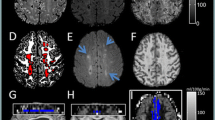

In 25 of the 36 patients, anemic infarction was diagnosed because of the absence of T2*-hypointense areas, while T1-weighted images showed curvilinear hyperintense lesions in the cerebral cortex (Fig. 1). In the remaining 11 patients, hemorrhagic conversion was noted because of the presence of T2*-hypointense areas. The hypointense areas of GRE-EPI T2*-weighted images did not correspond in their distribution to the hyperintense lesions on T1-weighted images (Fig. 2). Curvilinear T1 hyperintense lesions near the surface of the cerebral cortex did not show hypointensity on GRE-EPI T2*-weighted images in any of the patients, while there were signal intensity changes in the depth of infarcted gyri, which gave hypointensity on GRE-EPI T2*-weighted images and hyperintensity on T1-weighted images.

A 70-year-old man with nonhemorrhagic cerebral infarction in the territory of the right middle cerebral artery, at 28 days after the onset. a T1-weighted image shows curvilinear hyperintense lesions in the cerebral cortex. b T2-weighted image shows relatively low signal cortical lesions and hyperintense area in the white matter. c GRE-EPI T2*-weighted image reveals no noticeable area of hypointensity in the infarct. A small hypointense area representing old lacunar hemorrhage is seen in the right thalamus

A 73-year-old woman with cerebral infarction with hemorrhagic conversion in the territory of the right middle cerebral artery, at 37 days after the onset. a T1-weighted image shows hyperintense lesions in the cerebral cortex. b T2-weighted image shows hypointense lesions in the deep parts of infarcted gyri. c GRE-EPI T2*-weighted image reveals prominently hypointense lesions in the deep parts of infarcted gyri. Hypointense susceptibility artifact is not evident at the crests of the infarcted gyri